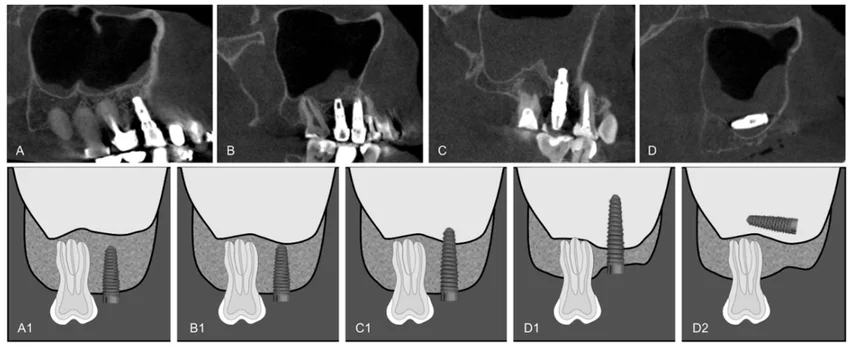

3️⃣ 상악동과의 거리가 부족한 경우

특히 위 어금니 부위는

상악동과의 거리 확보가 중요합니다.

Lucas et al, Evaluation of the Maxillary Sinus of Patients with Maxillary Posterior Implants: A CBCT Cross-Sectional Study, 2022

4️⃣ 초기 고정이 어려운 골질

임플란트는 식립 직후 안정적인 고정력이 중요합니다.

골 밀도가 낮은 경우 보강이 필요할 수 있습니다.